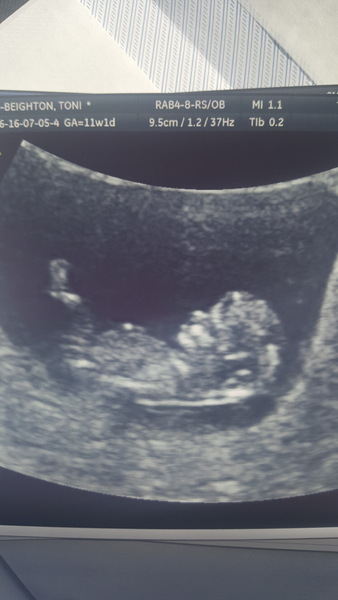

Welcome back MissClarke! I agree with the others, 8/9 weeks is a good time, much before that and there's not really anything to see. Also, if all looks good at 8 weeks that's when the stats say there is a big reduction in MC risk. However, I'll give my cautionary tale - I decided not to bother this time with an early scan as I had one at 9.5 weeks in my last pregnancy and they said it all looked great (it was a consultant scanning btw so as good as it gets), but then at 12 weeks they found incompatible with life abnormalities, which had been there from about 5/6 weeks but not visible and diagnosable until at least 11 weeks. So for me it was false reassurance in that (admittedly, rare) situation, but I now wouldn't feel very reassured by an early scan as I know that there's a lot they just can't tell at that stage.